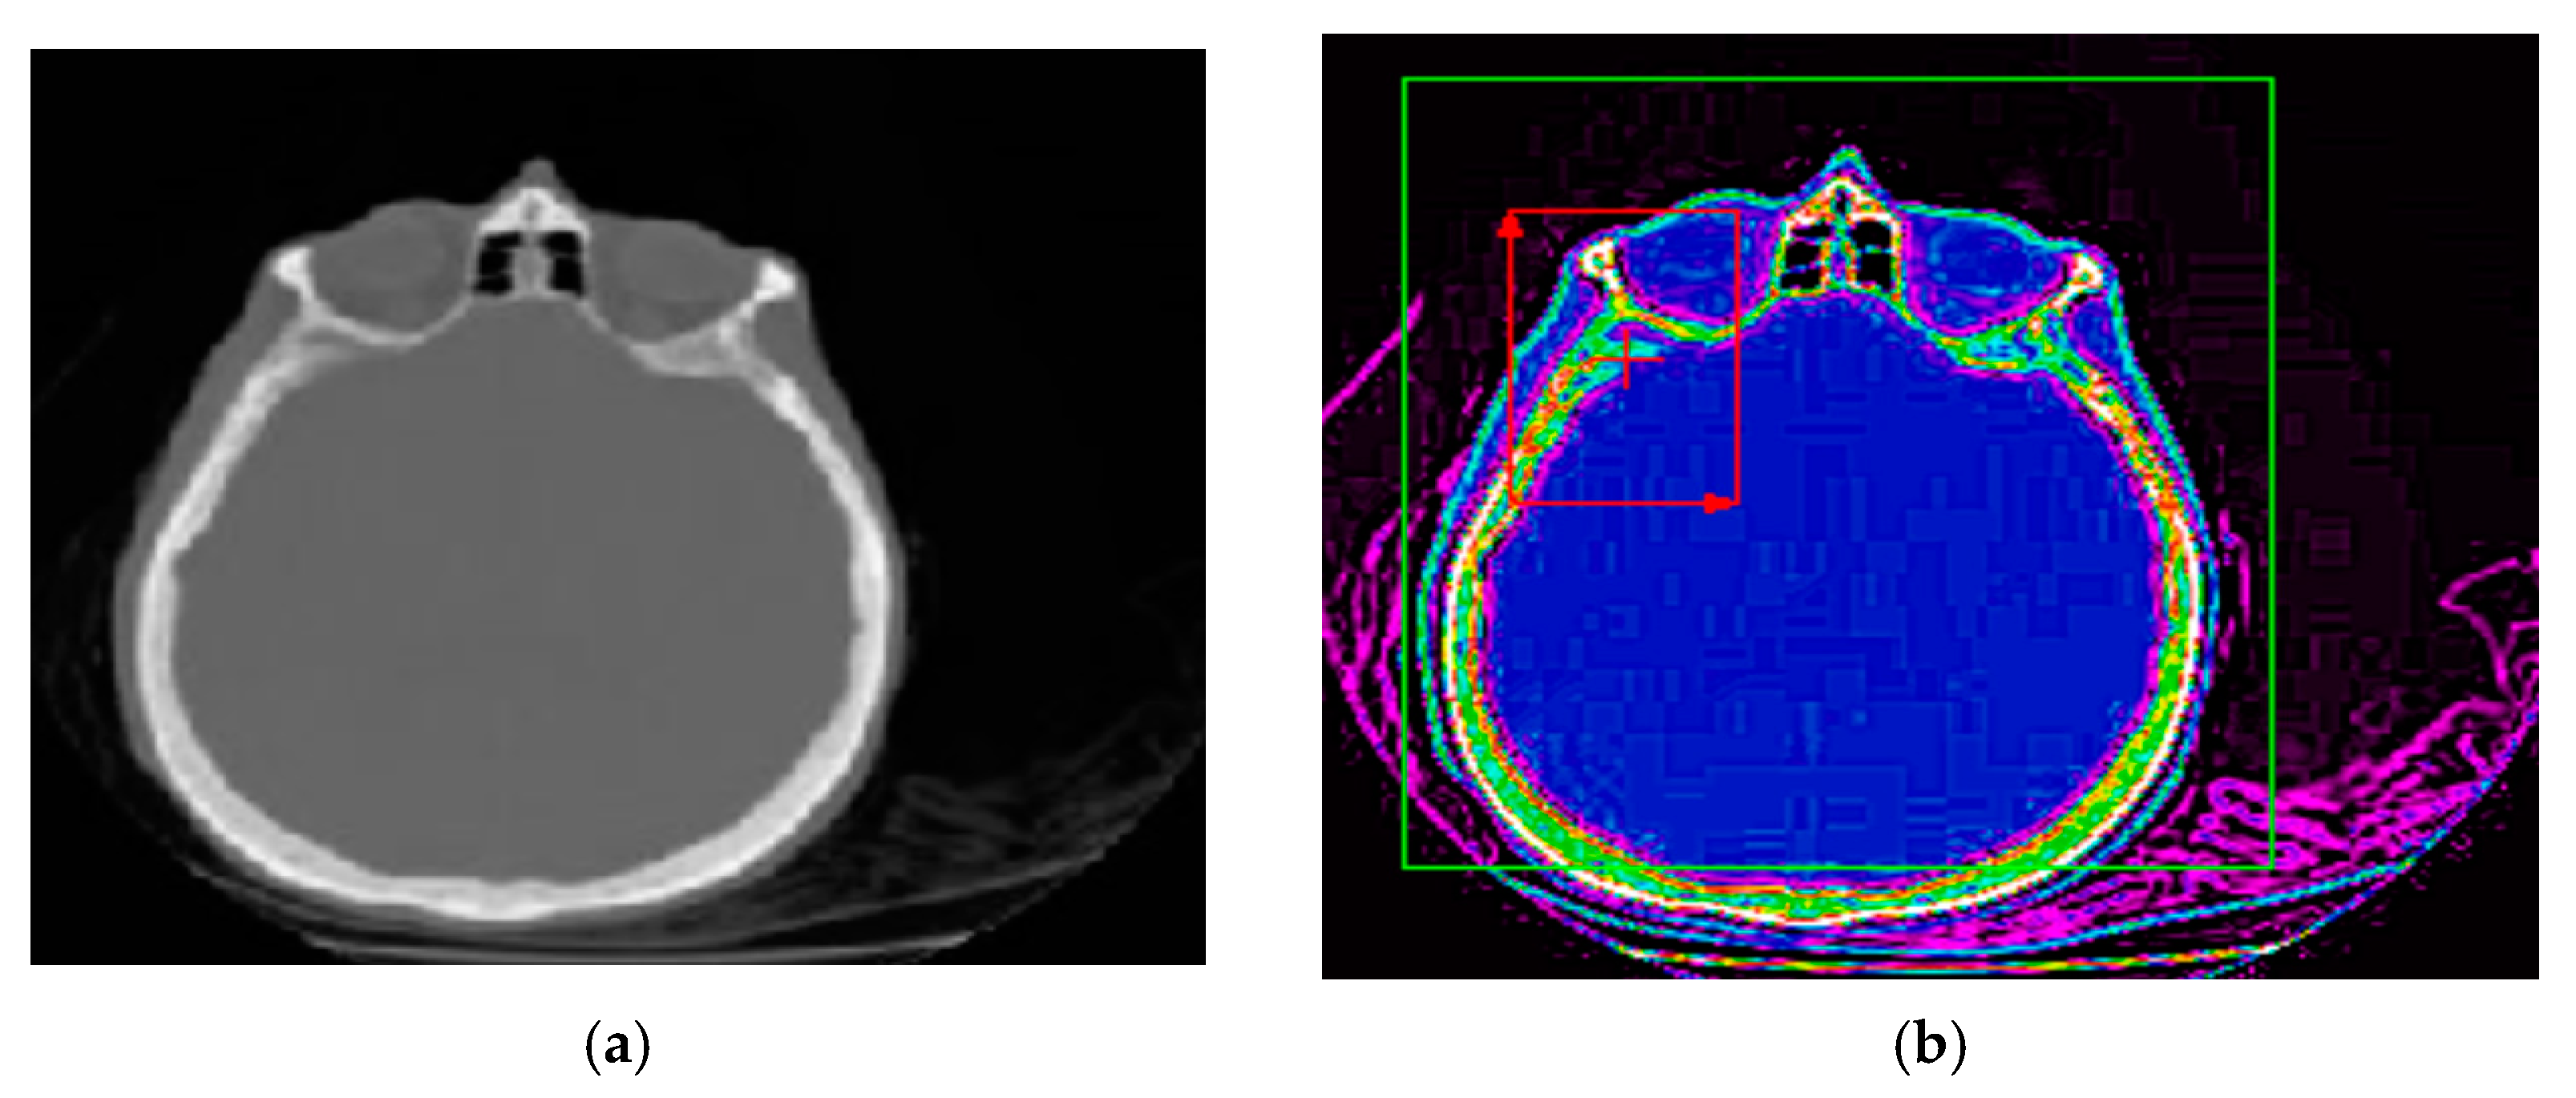

The proposed method for improving images with modified Wiener filter and nonlinear cellular network can be applied with success also with low contrast CT (computer tomograph) images. The improvement of tomographic image quality aims at obtaining superior visibility of the image components, the adaptive increase of the contrast, in order to be interpreted as easily as possible by the specialist doctor. Figure 7, Figure 8 and Figure 9 show the results obtained in the case of such images.

Imaging techniques are especially useful for interpreting biomedical CT/MRI images. The improvement of the quality of the tomographic images aims at obtaining a superior visibility of the image components, the adaptive increase of the contrast, to be interpreted as easily as possible by the specialist doctor. In the case of CT images, when the contrast is satisfactory ( λ = 0.05 ) , it is necessary to preprocess the image using the Wiener filter proposed in the article and nonlinear cellular network. Thus, image analysis after edge detection in preprocessed images can be facilitated. Based on the presented results, the validity of the proposed method for improvement of medical images can be found by the simultaneous use of the modified Wiener filter described in the article and cellular neural networks, for concrete applications in CT medical imaging.

Figure 8. (a) Initial image with low contrast; (b) improved image—CT cranial layer image processed with modified Wiener filter; (c) CT cranial layer image processed with the combined algorithm between the modified Wiener filter and the nonlinear cellular network.